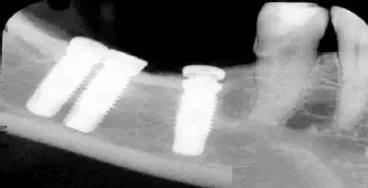

异物伪影

主要为密度差别极大的物体,如金属和人体组织一起扫描时所造成,伪影的特点是沿着高密度物体呈放射状排列。有时图像上不一定能直接看到目标异物,但只要仔细观察伪影的放射状方向,即能找到异物的来源。